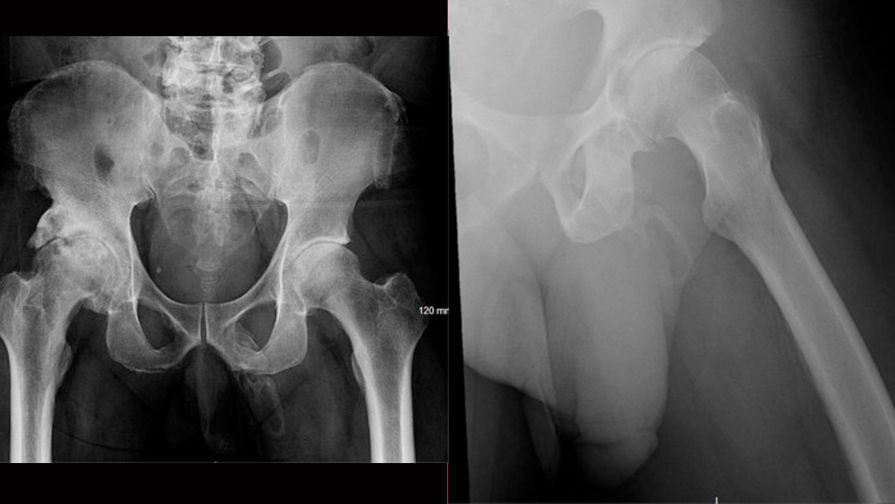

Во время осмотра он не жаловался на боль в области гениталий, врачи не выявили никаких припухлостей, выделений или других подозрительных признаков. Однако, сделав рентген тазовой области, они обнаружили, что вдоль полового члена мужчины сформировалась «обширная, похожая на бляшку область кальцификации».